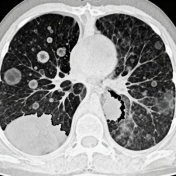

简单说,肺结节就是从CT片子上看到的、肺里那些直径小于3厘米的圆形或类圆形小阴影。

2.看密度

(1)实性结节:像个“实心球”,边界清晰,这类结节恶性率相对较低

(2)纯磨玻璃结节(pGGN):像云雾一样半透明,年轻人常见,60%-90%是良性,多数生长缓慢

(3)部分实性结节(混合型):既有实性又有磨玻璃成分,被称为“磨中之王”,恶性风险相对较高,需要重点关注

3.看形态

(1)边界光滑、圆形:多半是良性

(2)边缘毛糙、有毛刺、分叶状:需要警惕

(3)血管征、空泡征、胸膜牵拉:这些专业术语背后,意味着恶性风险增加